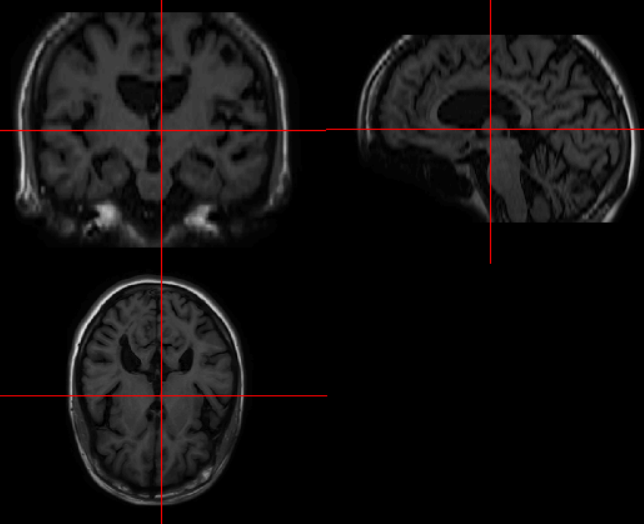

Found 420 validated image filenames.: '__get_item __ (index)' 함수를 호출하여, generator가 모델에 제공하는 내용을 살펴봄

x, y = train_generator.__getitem__(0)

plt.imshow(x[0]);

# Expected output

Clipping input data to the valid range for imshow with RGB data ([0..1] for floats or [0..255] for integers).